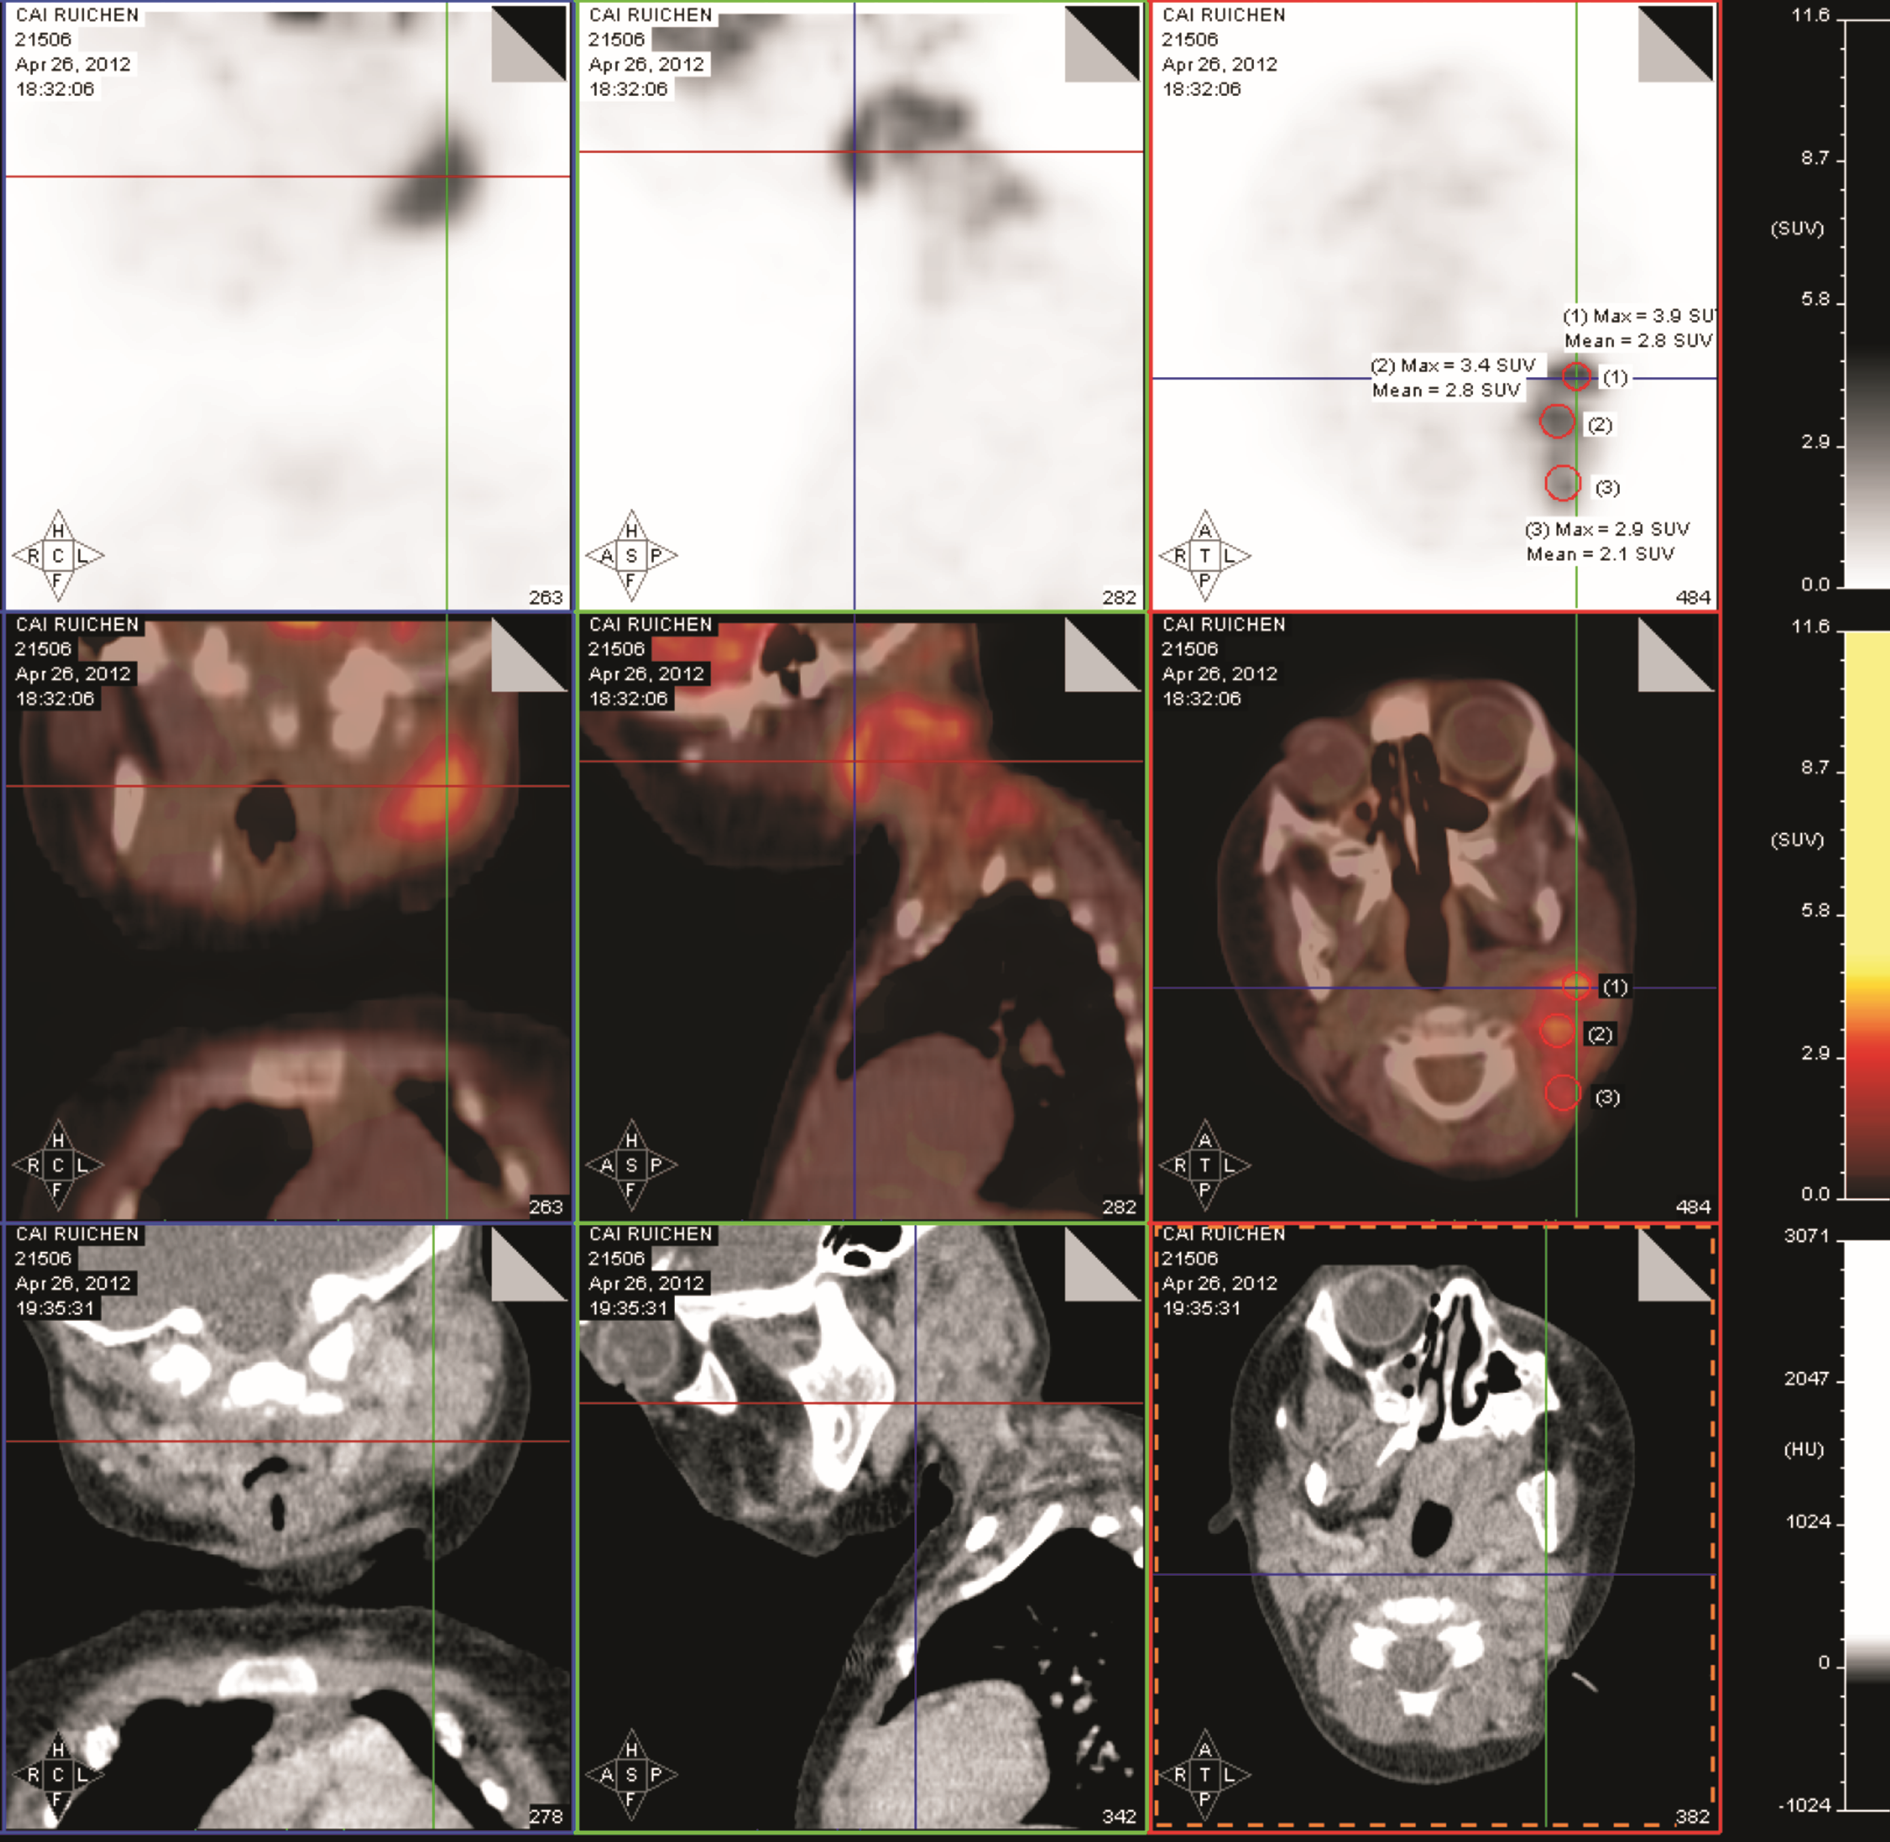

病情变化:采用BFM NHL 2000方案治疗,共6疗程。治疗结束后1个月因“皮疹伴反复发热10余天”再入院。特点:全身较密集红色丘疹伴瘙痒,部分化脓,右耳后、右侧腹股沟0.5~1.0 cm肿大淋巴结,质硬,无压痛,表面光滑。肝肋下3 cm,脾肋下刚触及。体温最高39.4℃,外院予抗菌、抗过敏等治疗,皮疹部分消退,仍发热,白细胞、血小板呈进行性升高,白细胞34.66~55×109/L,血小板646~950×109/L,血红蛋白 114 g/L,血沉:105 mm/h。骨髓涂片:骨髓增生活跃,淋巴瘤细胞占3.0%。PET/CT检查示:①全身多发肿大淋巴结葡萄糖代谢不同程度增高,考虑淋巴瘤影像学改变;②脾肿大、葡萄糖代谢弥漫性稍增高,考虑反应性改变。见 图1 图2。血培养阴性。抗菌治疗无效,2周后出现肛周脱皮,心脏超声提示冠状动脉扩张,诊断川崎病,予静脉注射免疫球蛋白 1 g/(kg·d)×2 d治疗,同时口服阿司匹林及潘生丁维持治疗,体温稳定,皮疹消失出院。

图1 疗程结束1个月后全身PET/CT图像

徐卫平(核医学科副主任医师):PET-CT检查提示全身多发中央及外周长骨骨髓不均匀放射性增高或减低,肝门区可见多发局灶性放射性浓聚,脾脏放射性药物摄取分布弥漫性增高,颈部、锁骨上窝、盆腔、腹股沟区多发淋巴结肿大,以左侧颈部淋巴结尤为显著,而腹股沟淋巴结代谢水平高,纵隔淋巴结肿大,但代谢水平不高。综合上述影像,考虑血液、淋巴系统恶性病变并骨髓、脾脏、肝门区淋巴结广泛浸润可能性大。